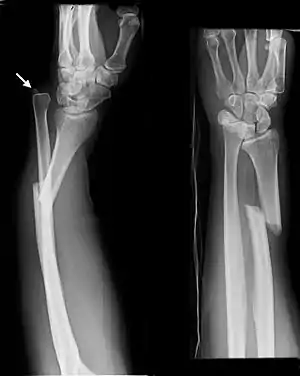

The Galeazzi fracture is a fracture of the distal third of the radius with dislocation of the distal radioulnar joint. It classically involves an isolated fracture of the junction of the distal third and middle third of the radius with associated subluxation or dislocation of the distal radio-ulnar joint; the injury disrupts the forearm axis joint.[1]

| Galeazzi fracture. Arrow points at the dislocated ulnar head | |

The dislocation of ulnar head in Galeazzi fracture dislocation may be dorsal (commoner) or volar (rare) depending on the mechanism of injury. If the fall is on the outstretched hand with forearm in pronation, the dislocation is dorsal, and if forearm is in supination at the time of injury, the dislocation is volar.[2]